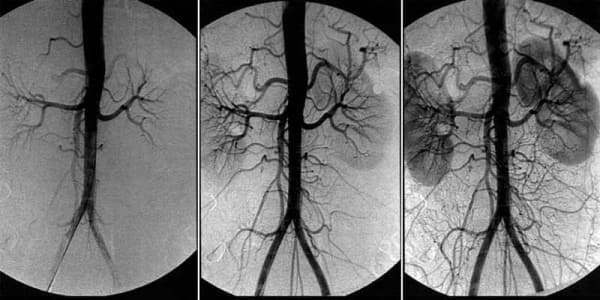

Was ist zu tun bei Kopfschmerzen, Tinnitus und tauben Gliedern? Anzeichen eines zerebralen vaskulären Angioödems.

Zerebrales vaskuläres Angioödem - das ist ein pathologischer Zustand, bei dem der normale Gefäßtonus und die Blutzirkulation in den Geweben des Gehirns gestört sind. In diesem Artikel erfahren Sie mehr über die Ursachen, Mechanismen und Symptome, wenn es Zeit ist, Alarm zu schlagen. Und auch über die schrecklichen Komplikationen dieser heimtückischen Krankheit und über den modernen Ansatz zur Behandlung, der allen zur Verfügung steht.

Ein Angioödem der Hirngefäße beeinträchtigt die Leistungsfähigkeit des gesamten Körpers. Aufgrund der unzureichenden Blutversorgung des Gehirns nimmt die Gesamtleistung ab, Schwäche tritt auf und wichtige Körpersysteme beginnen zu versagen.

Das Angioödem der Hirngefäße ist das erste Anzeichen für die allgemeine "Verschmutzung" der Gefäße des Körpers mit Cholesterin: die Atherosklerose. Die Gefäße des Gehirns sind die empfindlichsten und dünnsten, daher sind sie als erste davon betroffen.

Die Grundlage der Behandlung der Blutzirkulation in den Blutgefäßen des Gehirns ist die Reinigung der Blutgefäße des gesamten Körpers von angesammelten Verunreinigungen: Cholesterinablagerungen, Blutgerinnsel und Kalk.